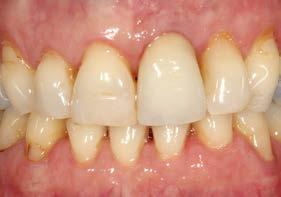

Tras 6 meses de oseointegración, se procedió a la confección de la prótesis definitiva. En aquel momento, hace 22 años, se eligió un biopilar microfresado y una corona metal-cerámica cementada, que representaban la mejor alternativa para garantizar un sellado adecuado y una estética satisfactoria en el sector anterior. En la actualidad, la opción preferible habría sido una prótesis atornillada con un elemento intermedio (transepitelial unitario) y una corona totalmente cerámica cementada a una interfase. No obstante, es importante contextualizar la decisión en función de la época en la que se finalizó el caso (Figuras 12 y 13).

La paciente ha permanecido en seguimiento y mantenimiento clínico durante 22 años, sin evidenciarse pérdidas óseas periimplantarias ni recesión gingival en torno al perfil de emergencia (Figura 14). En la actualidad, se realizó

Estos hallazgos confirman el éxito del procedimiento quirúrgico y de la posterior carga progresiva, con un mantenimiento óptimo de los tejidos duros y blandos a lo largo de más de dos décadas (Figura 15). Los cambios entre el momento inicial y el final del tratamiento son evidentes, especialmente al comparar la imagen intraoral de la primera visita con la tomada a los 22 años, donde la mucosa que rodea al diente 21 —y posteriormente al implante— se muestra engrosada, en buen estado de salud y con una estética destacable. Asimismo, la comparación entre la radiografía inicial, que evidenciaba el fracaso del tratamiento de conductos del diente en posición 21, y la radiografía a los 22 años, que muestra el implante sin pérdidas óseas asociadas, resulta elocuente (Figuras 16 a 19).

Figuras 16 y 17. Comparación entre la imagen inicial —diente con cambio de coloración, encía inflamada y pérdida de grosor— y la obtenida a los 22 años, que muestra estabilidad y salud gingival con el implante.